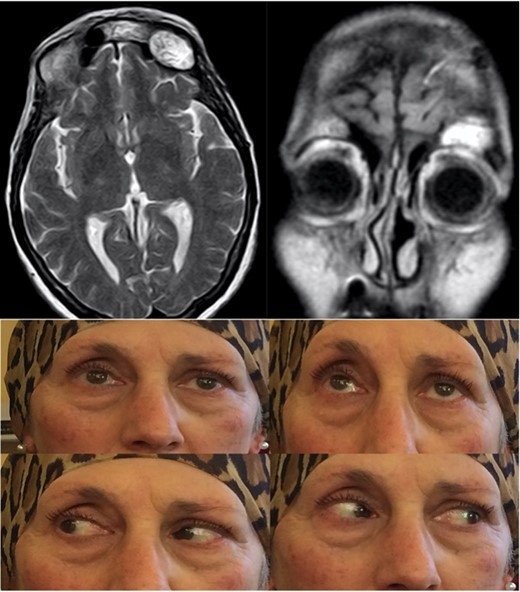

In the post-operative period the patient underwent a standard antibiotic prophylaxis (ceftriaxone 1 g × 2/die IV) for the successive 4 days and was discharged after 5 days with no neurological or systemic complication. The histological examination confirmed the intraoperative diagnosis of mucocele, and 1 month after the procedure, the patient showed a good improvement of the exophthalmos and ophthalmoplegia with a radiological evidence of complete sinus obliteration (Fig. 3).

Post-operative T2-weighted MRi showing the fat tissue filling the surgical cavity, with improvement of the ptosis and absence of diplopia.